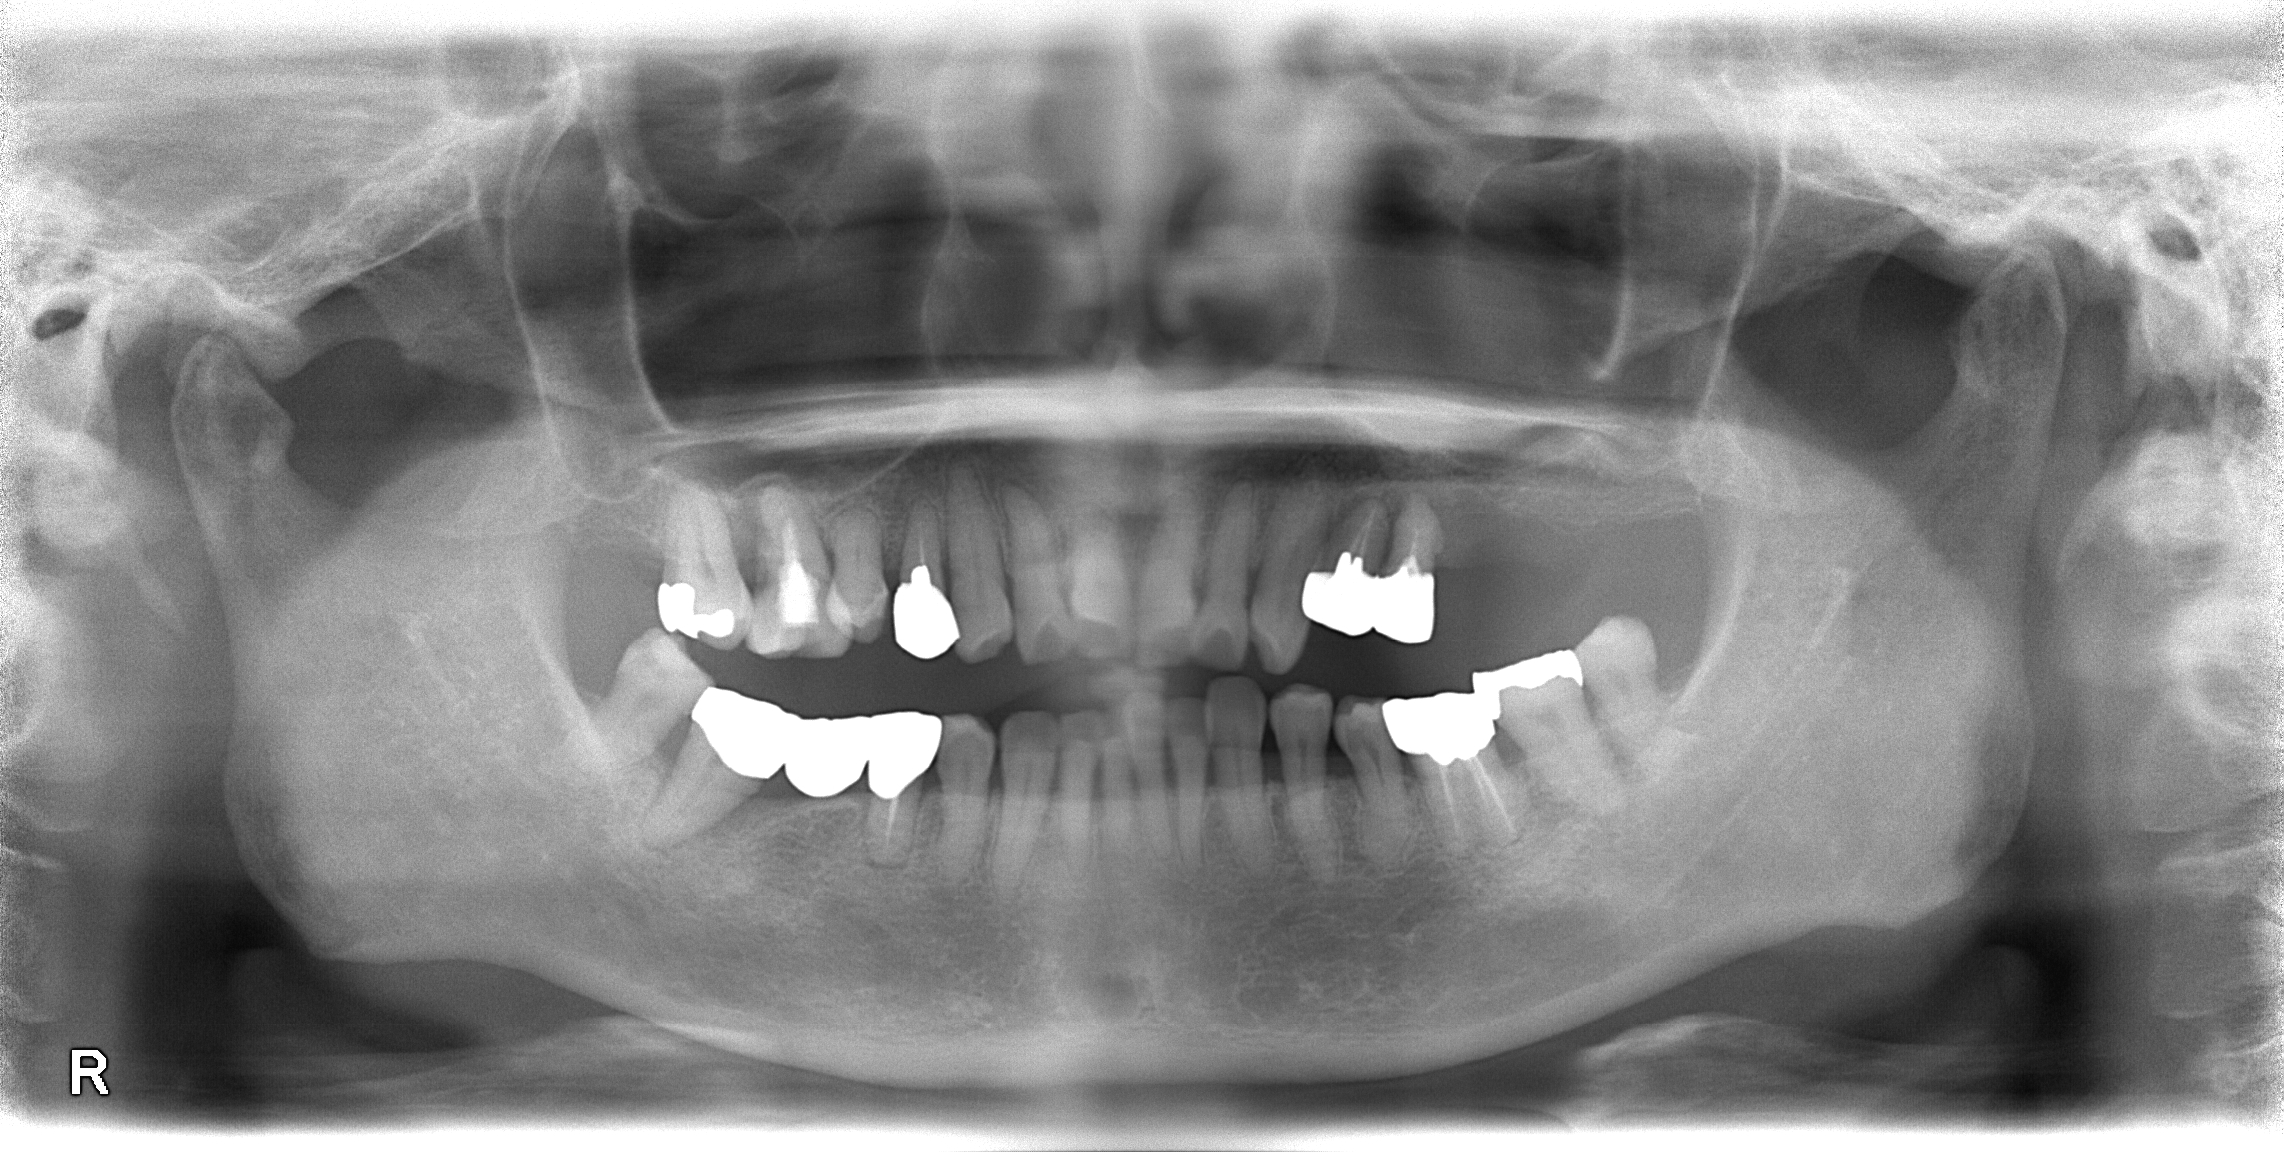

治療前

レントゲン写真になります。左上4、5部支える骨がなくなっています。

保存するのが難しいので残念ではありますが、抜歯させて頂きました。